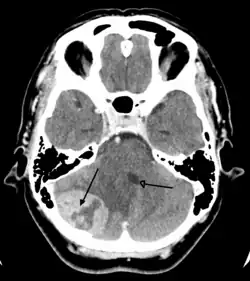

Imaging

Medical imaging plays a central role in the diagnosis of brain tumors. Early imaging methods – invasive and sometimes dangerous – such as pneumoencephalography and cerebral angiography have been replaced by non-invasive, high-resolution techniques, especially magnetic resonance imaging (MRI) and computed tomography (CT) scans.[42] MRI with contrast enhancement is the preferred imaging test in the diagnosis of brain tumors.[24][43] Glioblastomas usually enhance with contrast on T1 MRI weighted MRI imaging, and on T2 with FLAIR imaging showing hyperintense cerebral edema.[24] Low grade gliomas are usually hypointense on T1 MRI, and hyperintense with T2 with FLAIR MRI. Meningiomas are usually homogenously enhanced with dural thickening on MRI.[24]

Computed Tomography (CT) Scan – uses x-rays to take pictures from different angles and computer processing to combine the pictures into a 3D image. A CT scan usually serves as an alternative to MRI in cases where the patient cannot have an MRI due to claustrophobia or pacemaker. Compared to MRI, a CT scan shows a more detailed image of the bone structures near the tumor and can be used to measure the tumor's size.[51] Like an MRI, a contrast dye may also be injected into the veins or ingested by mouth before a CT scan to better outline any tumors that may be present. CT scans use contrast materials that are iodine-based and barium sulfate compounds. The downside of using CT scans as opposed to MRI is that some brain tumors do not show up well on CT scans because some intra-axial masses are faint and resemble normal brain tissue. In some scenarios, brain tumors in CT scans may be mistaken for infarction, infection, and demyelination. To suspect that an intra-axial mass is a brain tumor instead of other possibilities, there must be unexplained calcifications in the brain, preservation of the cortex, and disproportionate mass effect.[52]